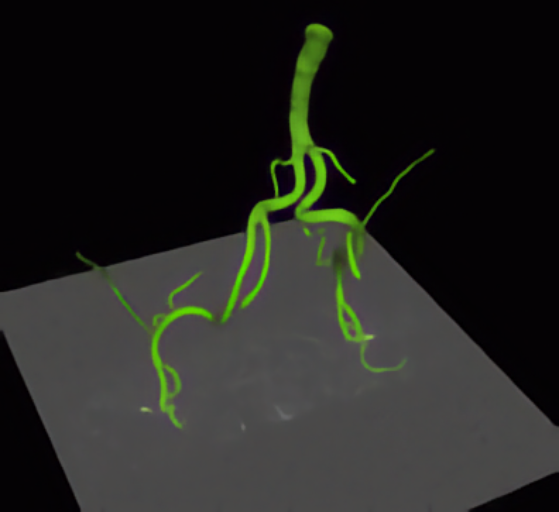

QuantVessel

Quantification of the Morphology of Human Vessels from 3D Tomographic Image Data (DFG Project)

Development of model-based approaches for accurate quantification of the 3D morphology of human blood vessels from 3D tomographic images (e.g., 3D CTA, 3D MRA). The approaches combine 3D cylindrical intensity models with incremental model fitting. The main application domain is the quantification of the aortic arch and its main bifurcating branches for improved operation planning using stent grafts.

Biesdorf A, Rohr K, von Tengg-Kobligk H, and Wörz S

Proc. 13th Internat. Conf. on Medical Image Computing and Computer-Assisted Intervention (MICCAI'2010)